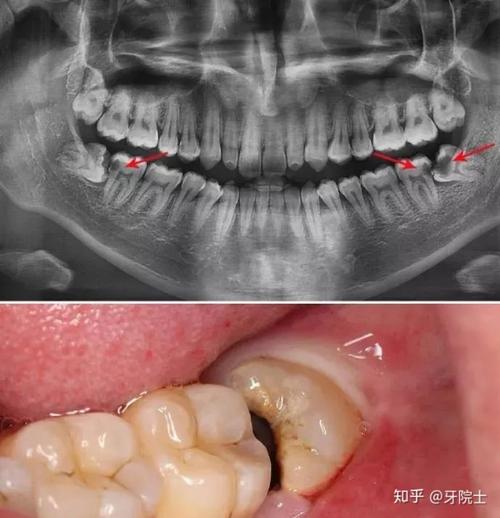

近中阻生智齿

水平阻生智齿

阻生智齿图片

阻生智齿不拔会变得怎么样?

阻生智齿